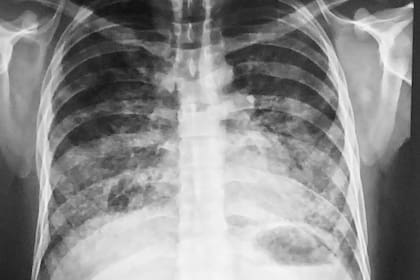

Como en todos esos países, se entiende como un caso confirmado para notificar cuando se trate de un paciente con un cuadro respiratorio con una imagen de tórax similar a una neumonía bilateral, pero en el que las pruebas diagnósticas descarten una infección y la persona, que de otro modo tenga un buen estado de salud general, haya fumado cigarrillo electrónico por lo menos una vez en los últimos 90 días, según explicaron a LA NACION.